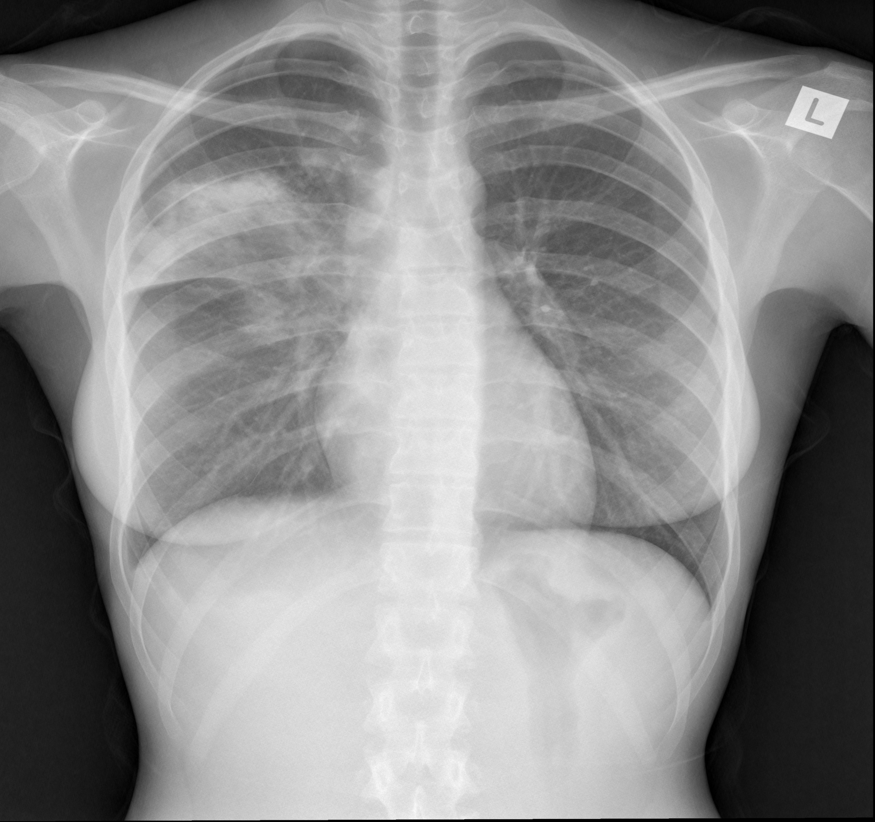

What is this showing?

AP errect

LUL collapse- collapses anteirorly becoming a thin sheet of tissue –> “Veil sign”

Loss of silhouette sign of aortic knuckle

General opacity on the left